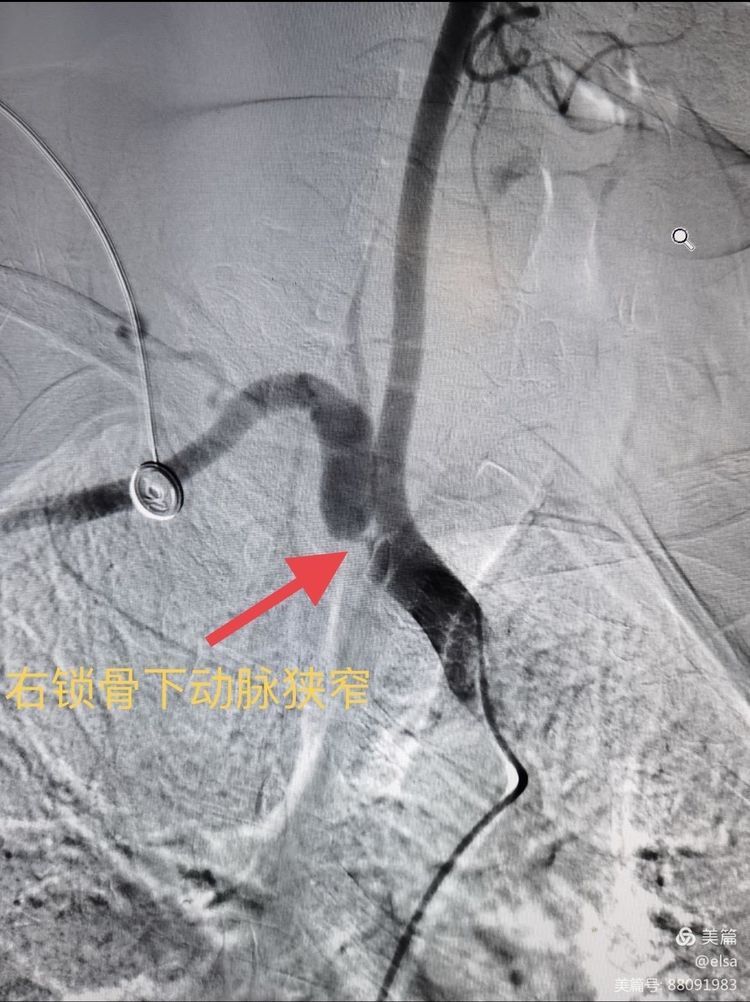

7月15日,血管介入科刘顺帆主任、彭怀玉教授、钟勇进副主任医师给予患者行经股动脉插管全脑血管造影示:右锁骨动脉起始部重度狭窄,狭窄约95%,其远端血流由同侧椎动脉盗血形成,闭塞段长约2•0cm。

右锁骨下动脉狭窄、闭塞。